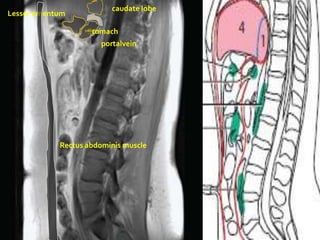

caudate lobe

Lesser omentum

Stomach

portalvein

Rectus abdominis muscle